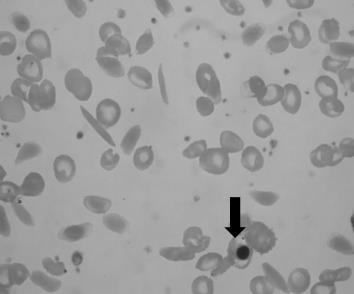

No diagnóstico da anemia falciforme, alguns achados são observáveis no esfregaço de sangue periférico. O indicado pela seta denomina-se: